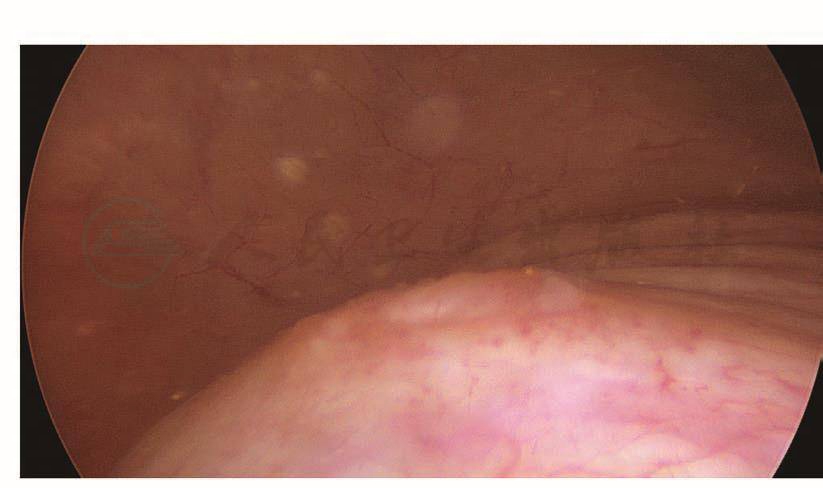

LTH手术时,如果患者既往有腹式盆腔手术,由于组织粘连就有可能增加膀胱损伤的几率。术组配合不默契,也会增加膀胱损伤的危险性。笔者早期在做一例LTH时,由于助手没有把子宫推向盆腔正中,在剪开膀胱腹膜反折时不慎将膀胱剪开20mm(图101、图102)。术中发现膀胱损伤及时修补,预后极佳,但如果在术中没有发现损伤,则很可能出现膀胱阴道瘘。笔者所在单位施行的一例LTH,手术过程顺利,术后两天拔除尿管,阴道流液增多,怀疑膀胱阴道瘘,做膀胱镜检查没有发现明显的瘘孔,但阴道流液持续增多,两周后再做膀胱镜检查,从阴道残端插入探针,膀胱镜下可以清楚地看到探针,证实是膀胱阴道瘘。该例之所以出现术后膀胱阴道瘘,是由于损伤极小,术中没有引起注意,没有及时修补。

图101 膀胱穿孔

图102 穿孔内的导尿管气囊